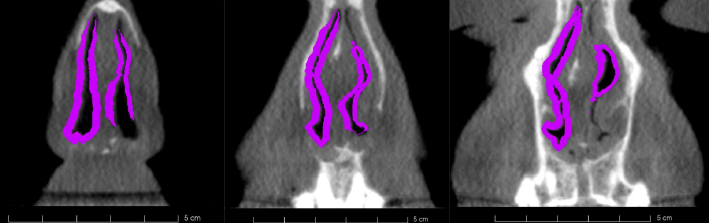

Figure 4 shows optimization results with the LB method based on the CT dataset of the patient for whom CT, MR, Rhinomanometry and acoustic Rhinometry data were available. Coronal slices close to the nasal valve are depicted. Magenta shows the calculated resection volume.

Figure 4: Optimization results of the CT data of the patient with Rhinomanometry and Rhinometry data. Coronal airflow cross-sections. Background: CT image, Magenta: suggested resection volume.